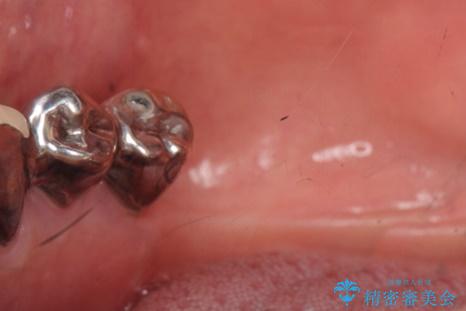

- 下の前歯(左下2)と奥歯の動揺がひどくなってきたことを主訴に来院された患者様です。

精査したところ、前歯の咬み合わせが反対になっていること、下の奥歯(下顎両側67)が4本欠損していることから動揺が生じていました。

入れ歯も抵抗があるとのことから、相談を重ね、今の状態では保存不可能な下の前歯(左下2)を抜去し、ブリッジや連結補綴により動揺を抑えることにしました。